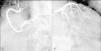

A conventional resting electrocardiogram showed sinus rhythm, heart rate of 78 bpm and left ventricular overload. A chest X-ray revealed a normal cardiothoracic index and no signs of pulmonary congestion. A resting Doppler echocardiogram revealed aortic regurgitation, defined as moderate based on the slope of the deceleration curve in diastole (slope 354 cm/s2) and no holodiastolic retrograde blood flow in the abdominal aorta (score 6). The eccentricity of the regurgitant jet limited the possibility of using the width and area of the aortic regurgitation jet as parameters to classify the severity of the valvulopathy (Figure 1A). There was eccentric LV hypertrophy but no signs suggestive of pulmonary arterial hypertension. The following chamber diameters and volumes were calculated: left atrial diameter 38 mm, end-diastolic LV diameter 64 mm, end-systolic LV diameter 42 mm, end-diastolic LV volume 142 ml, and end-systolic LV volume 57 ml. Global systolic function defined by ejection fraction as calculated by Simpson's method was 59%. Peak and mean aortic valve gradients were not calculated (Figure 1B).

In order to confirm the role of systolic dysfunction during exercise as the cause of the plateau followed by a fall in oxygen pulse during CPET, a Doppler echocardiographic study during dynamic physical exercise was performed using the same exercise protocol employed for CPET. Under these conditions, the following results were obtained at peak exercise compared to rest: increases in LV end-diastolic diameter from 64 to 68 mm, in LV end-systolic volume from 57 to 91 ml, and in end-diastolic volume from 142 to 159 ml, and a fall in ejection fraction from 59 to 42% (Figure 1C). LV ejection fraction was also evaluated by radioisotope ventriculography at rest and during dynamic physical exercise, with 61% being observed at rest and 47% at peak exercise.